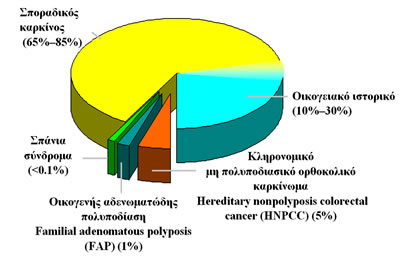

Οι περισσότερες περιπτώσεις καρκίνου του παχέος εντέρου είναι σποραδικές (65%–85%) (Εικόνα 5).

Στον οικογενή μη κληρονομικό καρκίνο (10-30%) υπάρχει άνω του μετρίου προδιάθεση για ανάπτυξη καρκίνου αλλά η γενετική βλάβη δεν είναι πλήρως καθορισμένη, όπως συμβαίνει στα καθαυτό κληρονομικά γενετικά σύνδρομα του ορθοκολικού καρκίνου (5-6%), στα οποία η εμφάνιση του καρκίνου γίνεται σε μικρότερη σχετικά ηλικία (Εικόνα 5).

Εικόνα 5.

Σποραδικός, οικογενής και κληρονομικός καρκίνος του παχέος εντέρου